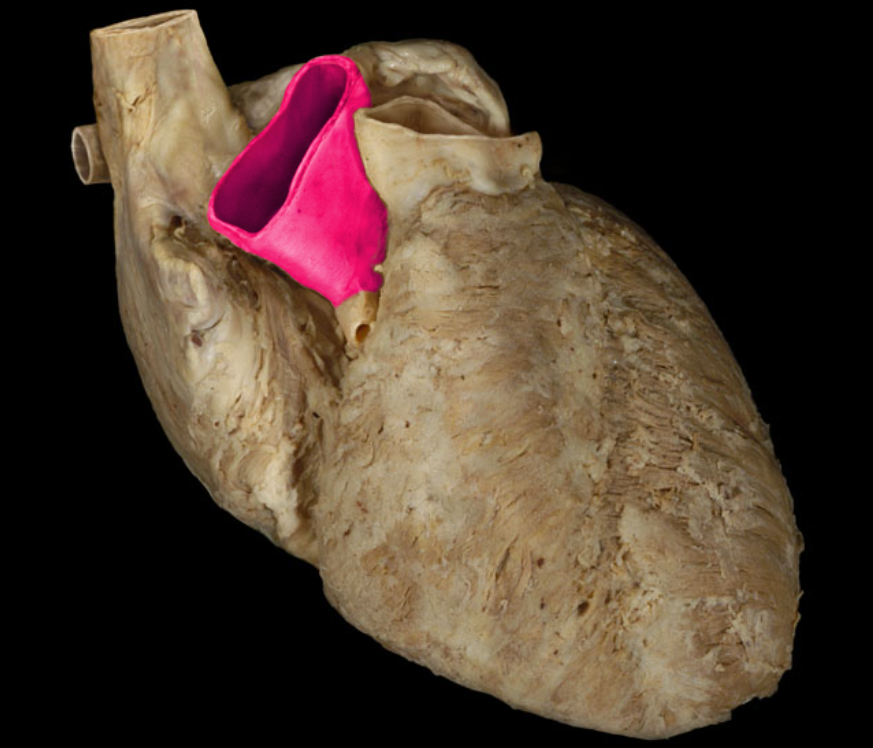

The auricles are flap-like projection off of the___and serve to increase their blood volume.

atria

Left auricle

Right auricle

Left auricle

Right auricle